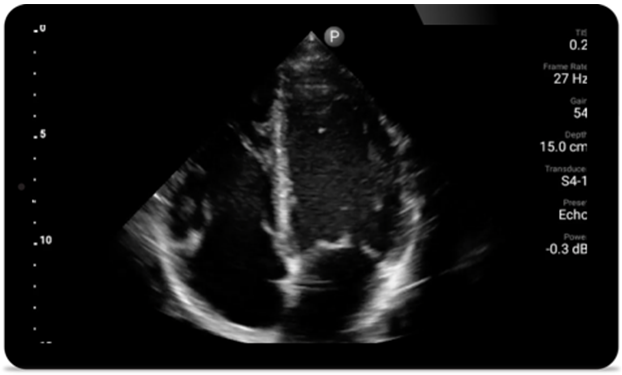

Jede Sekunde zählt in der Kardiologie

Herzinfarktpatienten benötigen unmittelbare Versorgung. Mit den kardiologischen Presets von Lumify können Patienten schneller diagnostiziert werden, um ihre Prognose zu verbessern.